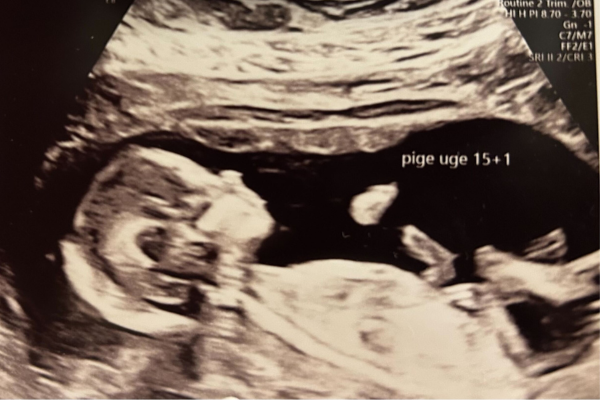

Uge 15+0 – 15+6

Din baby vejer nu cirka 100 gram og måler cirka 10-12 cm. Hvis dit barn har anlæg for mørkt hår, begynder pigmenten nu at blive produceret. Måske begynder håret så småt at vokse, selvom det for mange børn først kommer flere måneder efter fødslen. Øjenbrynene dukker også op denne uge. Hele den lille krop og dens tynde hud er dækket af det farveløse lanugohår eller dun. Det hjælper barnet med at holde kropsvarmen, og når fødslen nærmer sig, så forsvinder det mere og mere. Gennem den tynde hud ses små, tynde blodårer. Lillehjernen og rygmarven er dannet. Barnet begynder at lagre kalcium, der senere bruges til udviklingen af skelettet og dets knoglemarv. Selvom barnet er omgivet af fostervand, øver det sig i at trække vejret. Nu kan det lille barn få tommelfingeren ind i munden. Barnet kan lave baglæns saltomortaler og sparker løs inde i maven. Benene er længere end armene, som kan nå hinanden hen over brystkassen.

Find ud af om du venter en dreng eller pige ved at få en kønsscanning. At kende sit barns køn kan fremme tilknytning, gøre forberedelserne lettere og skabe bedre forståelse hos søskende.